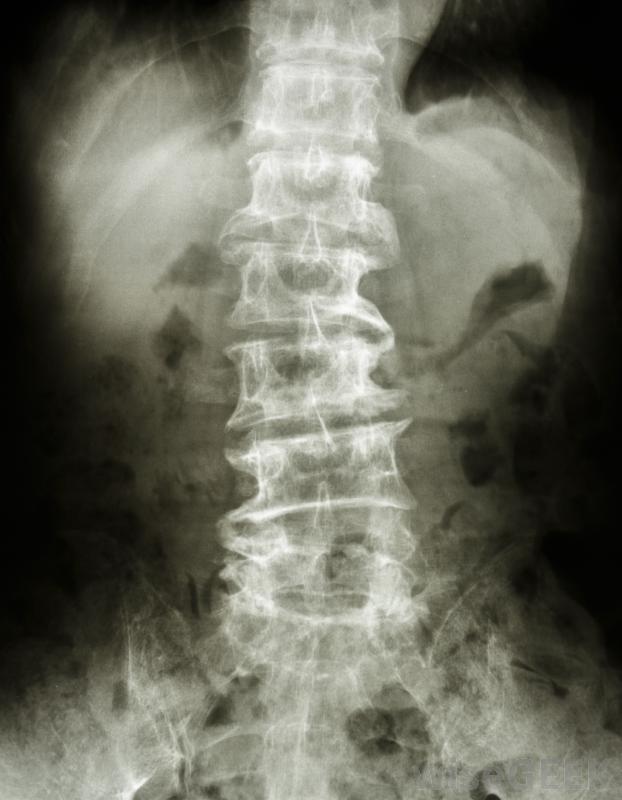

椎体切除术是一种外科手术,外科医生切除骨头和椎间盘,以减轻病人脊髓和神经的压力。作为手术的一部分,医生会切除一部分构成脊柱的骨段,以及与被切除的骨段相邻的椎间盘,以防止骨骼相互摩擦。为了填补骨和椎间盘切除后留下的空间,外科医生使用骨移植重建脊柱,这是一种用其他骨或骨替代物替换缺失骨组织的手术。

患者在椎体切除术后可能会出现喉咙痛此手术可用于治疗因骨刺导致颈椎管狭窄的患者,但它也可以在脊柱的其他部位进行,也可以用于治疗其他疾病。颈椎椎管位于颈部,是脊髓穿过的通道。也被称为骨赘,骨刺是从正常骨边缘发育并突出的骨段,当它们接触时伴随着神经和其他骨骼,会引起疼痛、麻木、刺痛等症状,有些人还会因为颈椎椎管狭窄而出现针扎感、手臂和手部无力等症状,严重者还可能失去对膀胱和肠道的控制,难以维持平衡

在椎体切除术中,患者将处于全身麻醉状态,不会感到疼痛。椎体切除术通常是在全身麻醉下进行的,患者无法感觉到手术。当病人仰卧时,外科医生在病人的颈部开一个小切口,开始椎体切除术。如果病人自身的部分骨组织用于植骨,可能需要另一个切口。然后,外科医生取出要取出的骨头上下的椎间盘,最后,外科医生用植骨填充空隙,支撑脊柱;有时金属板和螺钉用于额外支撑。